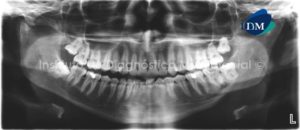

Paciente masculino de 65 años de edad es referido al Instituto de Diagnóstico Maxilofacial (IDM) para evaluación de problemas periodontales. A la evaluación de la radiografía panorámica se aprecia una imagen radiopaca de densidad de tejidos blandos, de forma redondeada proyectada en el antro del seno maxilar izquierdo, compatible con quiste de retención mucoso. Asimismo observamos reabsorción ósea alveolar moderada generalizada, con presencia de proceso osteolítico peri radicular a nivel de pieza 3.7 (Figura 1).